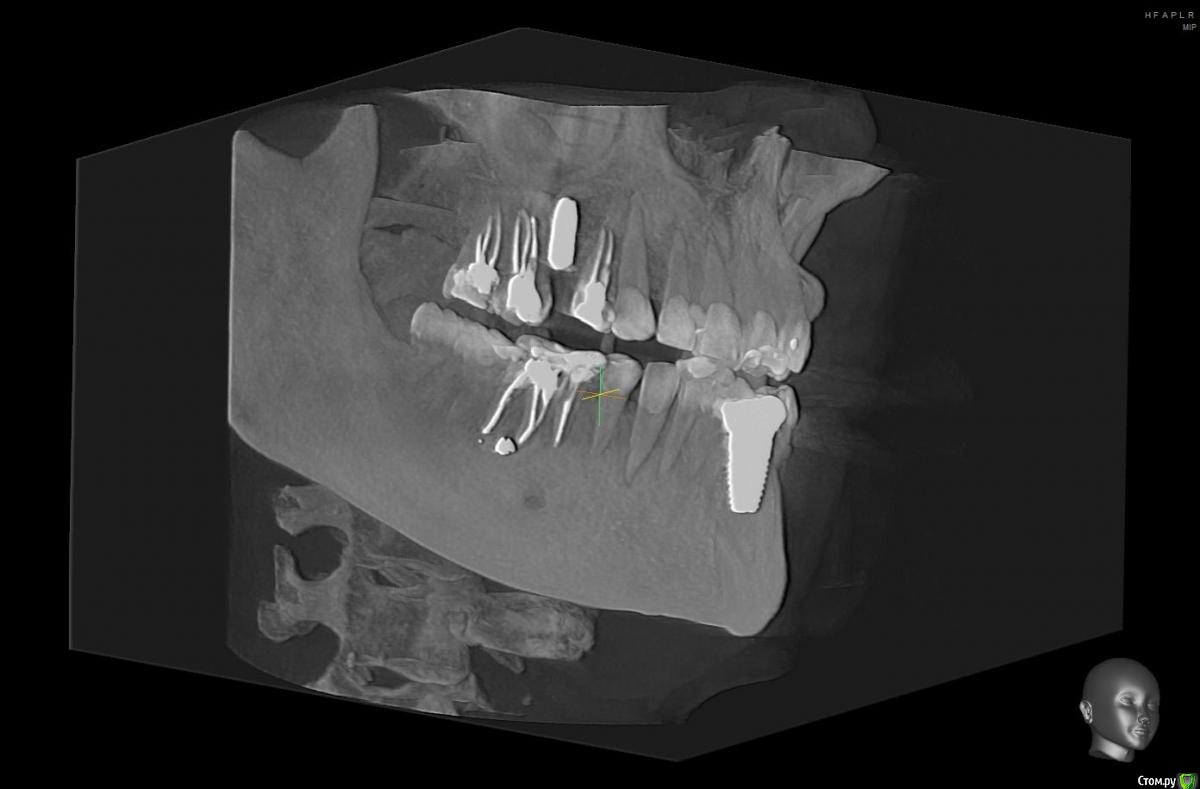

Tatiana72 Опубликовано 27 октября, 2020 Автор Поделиться Опубликовано 27 октября, 2020 Добрый вечер!Выкладываю скрины срезов Ссылка на исследованиеhttps://yadi.sk/d/ViQR0U6R2QjHzg Ссылка на комментарий

Дмитрий М Опубликовано 28 октября, 2020 Поделиться Опубликовано 28 октября, 2020 Добрый вечер!Выкладываю скрины срезовImage4.jpgImage5.jpgImage9.jpg Ссылка на исследованиеhttps://yadi.sk/d/ViQR0U6R2QjHzg не волнуйтесь всё хорошо, по КТ корень зуба не задетесть небольшой очаг разряжения на одном из апексов, обратитесь к стоматологу 1 Ссылка на комментарий